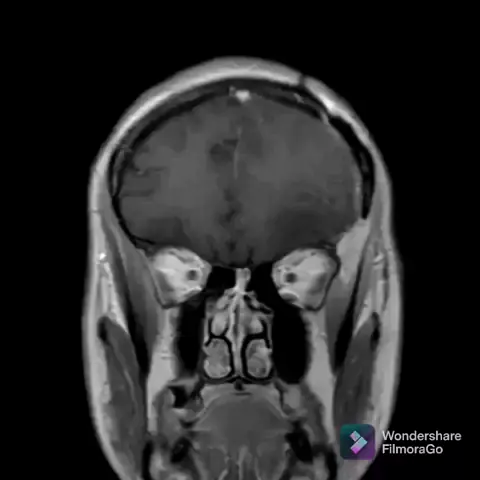

Tumor cerebral... #cena #kwai #love #movie